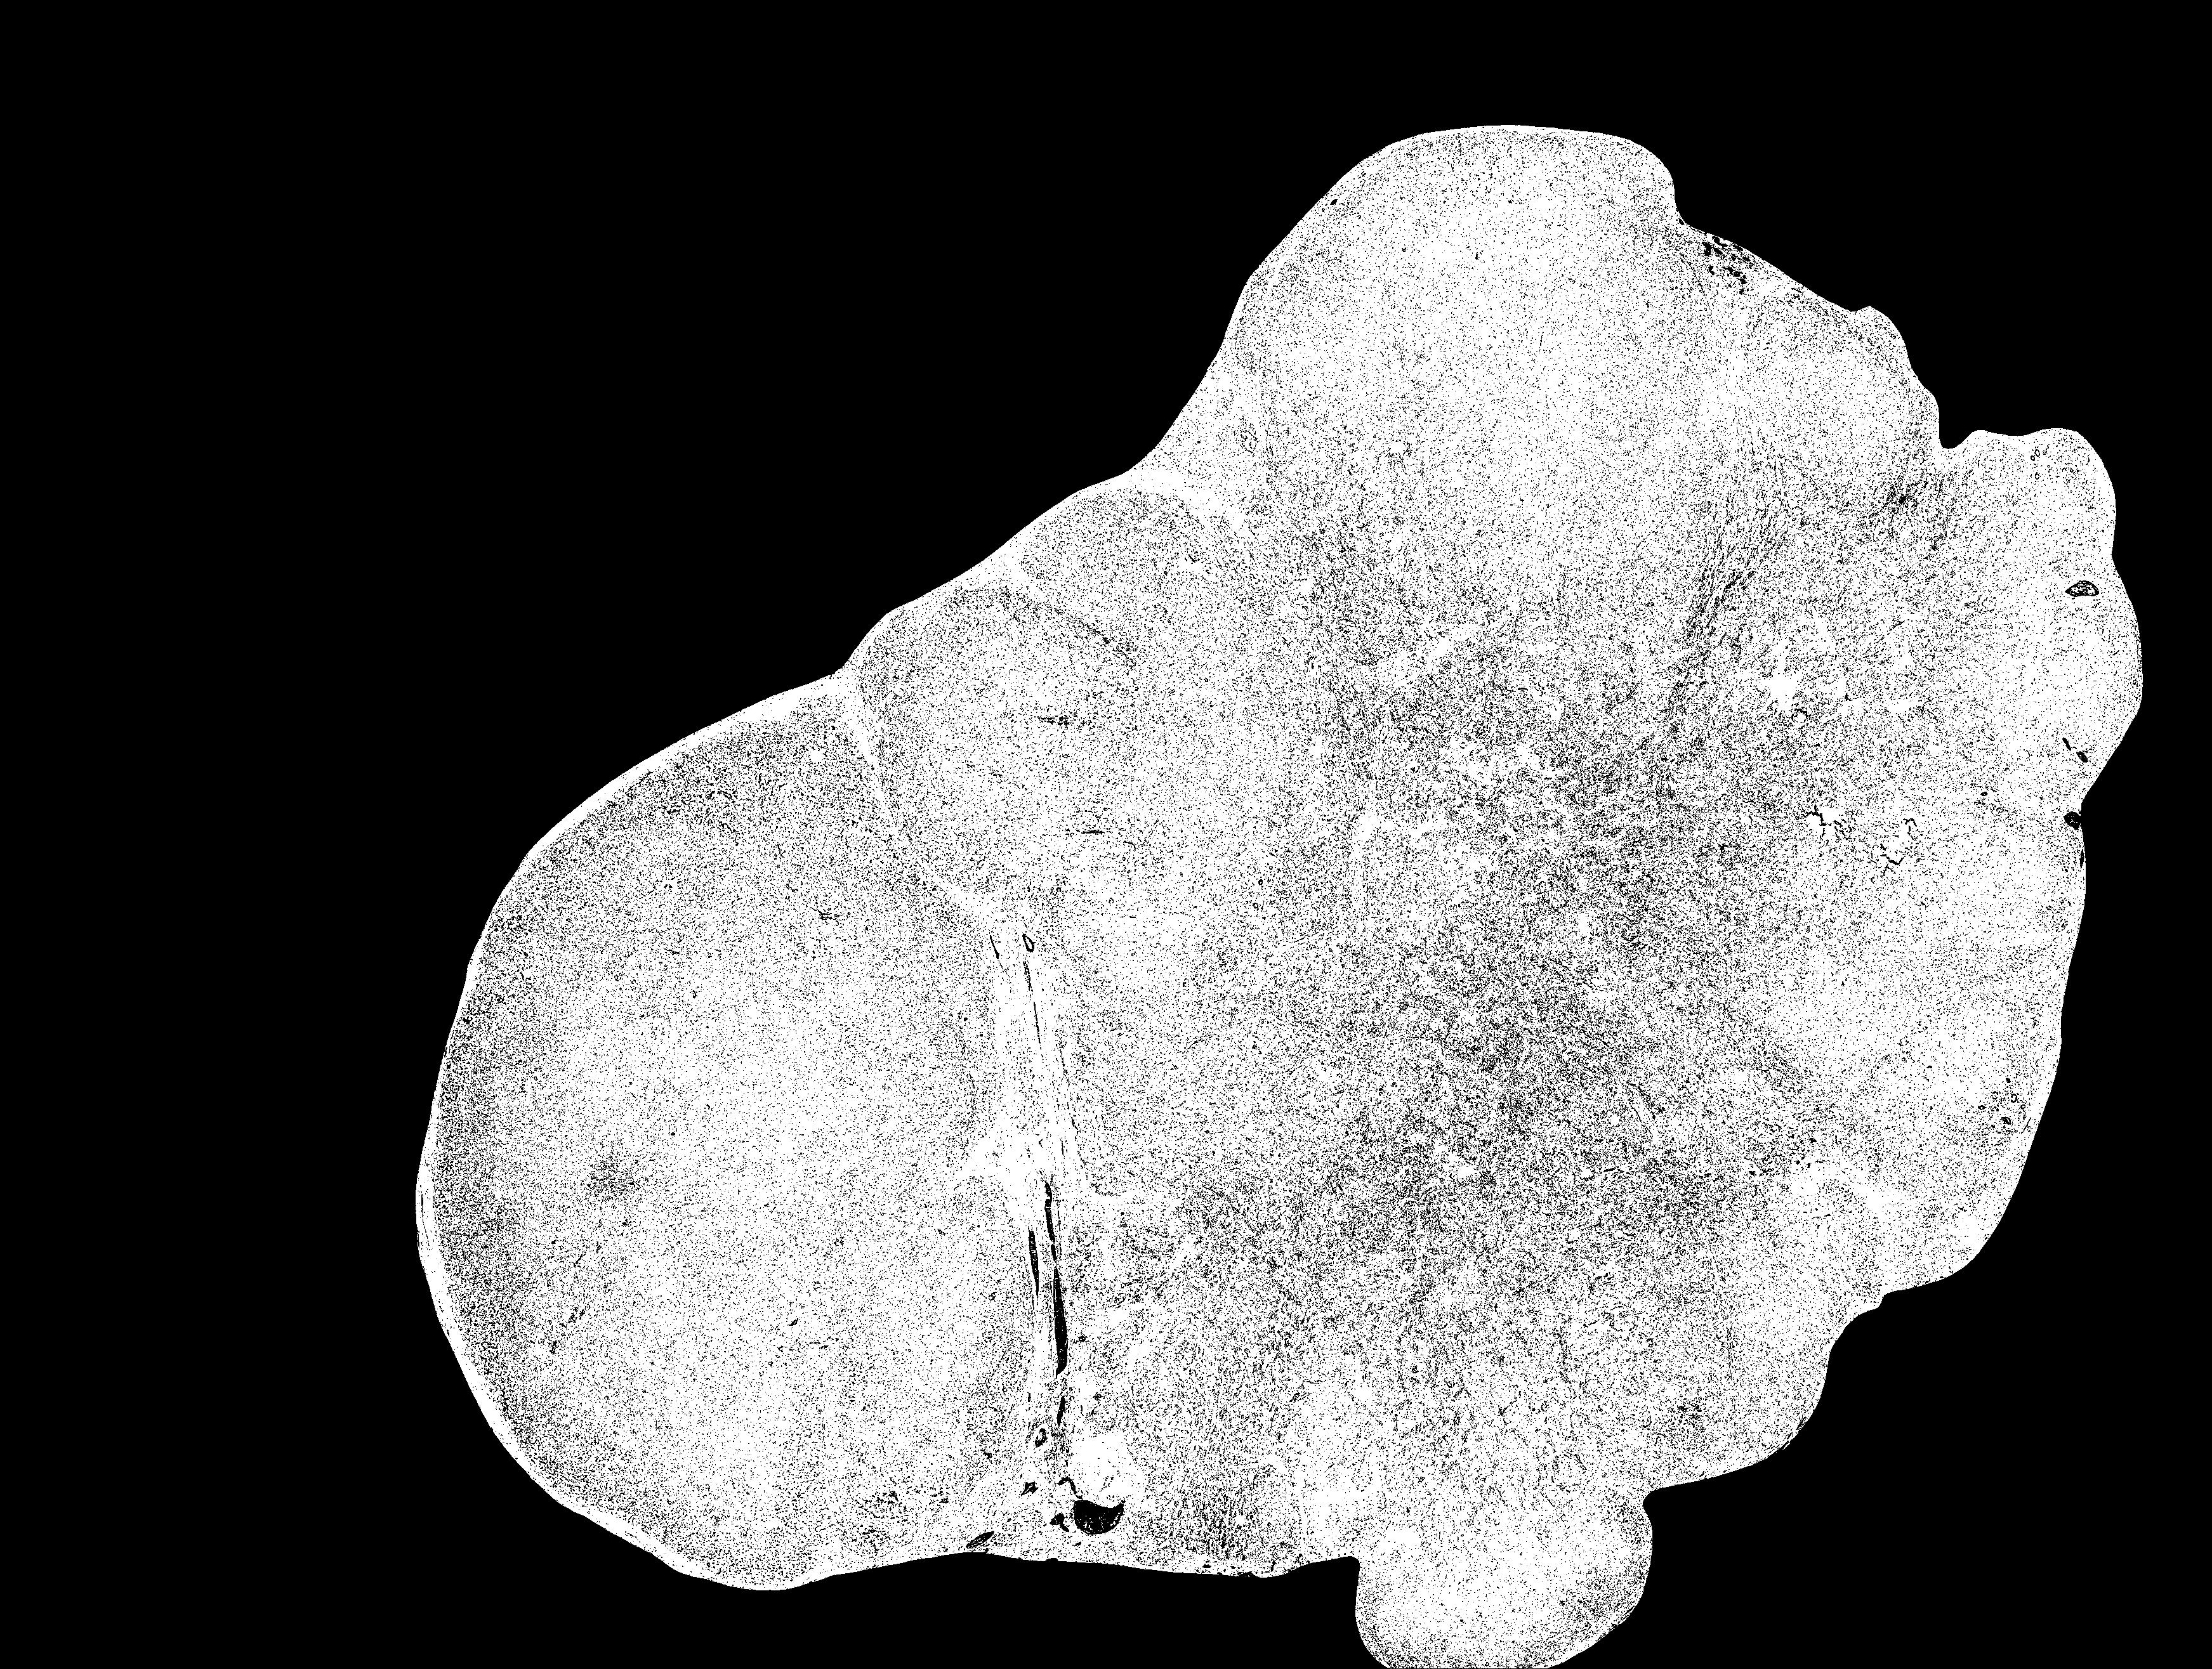

(a) Ground truth

(b) R18_U-Net (4096)

(c) TR-I

(d) HiTrans

4.2 Ablation study

The proposed hierarchical Tansformer encoder framework can learn global dependencies and bring muti-scale cues for the decoder during segmentation inference. In the ablation study, we removed the Transformer hierarchical add-on module, in order to evaluate the above argument, namely, that knowledge of global dependencies can enhance segmentation performance. Experiments without the add-on module using 512512 (Tab. 2, Exp. 1) and 40964096 (Tab. 2, Exp. 2) patches were conducted separately. Besides, an experiment using an architecture without Transformer encoder II was conducted (Tab. 2, Exp. 3). By comparing the experimental results, taking larger patches as input and using HiTrans to learn the global dependencies can lead to better segmentation results. Comparing with the results from add-on module dropped (Fig. 2, b) and Transformer encoder II dropped (Fig. 2, c) architecture, HiTrans can further improve the precision (Fig. 2, d) thanks to this regional and global dependency-aware architecture.